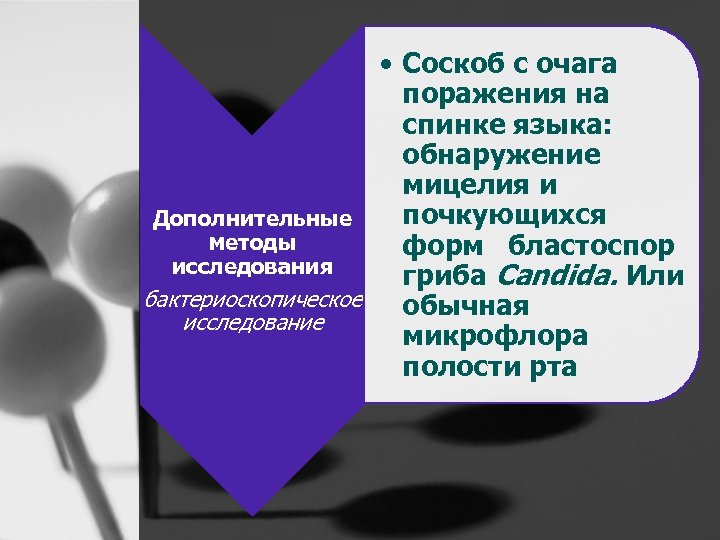

• Соскоб с очага поражения на спинке языка: обнаружение мицелия и почкующихся Дополнительные методы форм бластоспор исследования гриба Candida. Или бактериоскопическое обычная исследование микрофлора полости рта